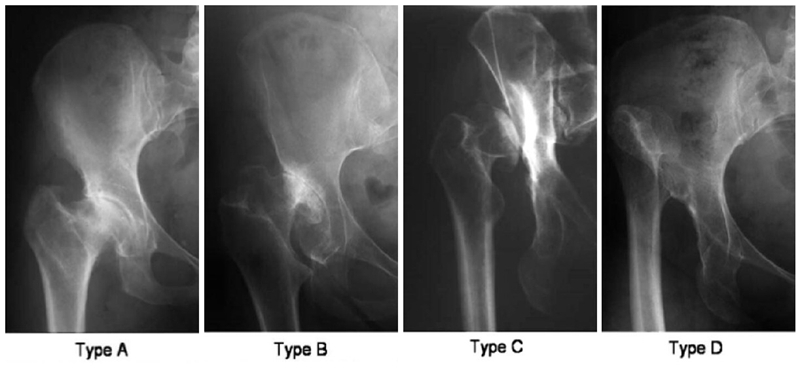

3、Eftekhar分型

Eftekhar分型最早于1978年提出,该分型方法基于股骨头脱位的程度把成人DDH分为以下4型:

A型:髋臼发育不良,髋臼轻度变长,伴有股骨头发育不良,没有假臼形成;

B型:半脱位的髋关节形成了假臼,假臼与真臼有重叠的部分;

C型:股骨头完全脱位,与髂骨形成高位、独立的假臼,真假臼之间没有重叠;

D型:股骨头向后上方完全脱位,但没有与髂骨形成假臼。